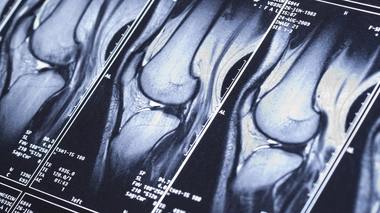

Rupture des ligaments croisés du genou : comment se déroule la chirurgie ?